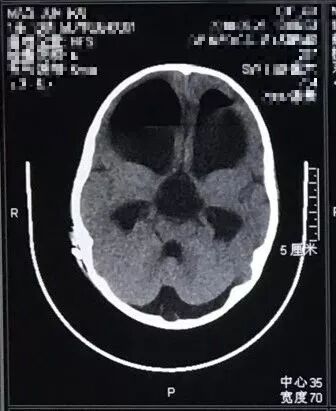

鞍上池囊肿

图片尺寸640x480

鞍上池蛛网膜囊肿的微创治疗